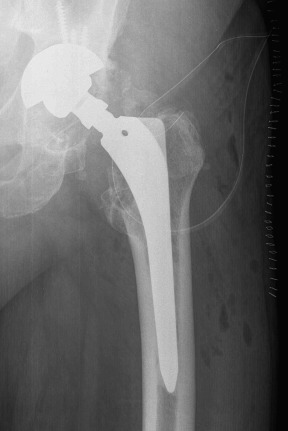

In September 2011 (ten years after primary THA), the patient came to our clinic complaining of hip pain. An important cup asymmetry that indicated wearing of the polyethylene was observed in the radiographic study (Fig. 1 ). The patient was 185 cm tall and weighed 110 kg (body mass index [BMI], 32.14 kg/m2 ). The patient underwent revision of the acetabular component and an exchange of the polyethylene component. Significant metallosis and loosening of the acetabular component was observed. The selected components for the revision were a 58 mm Trilogy® (Zimmer, Winterthur, Switzerland) acetabular shell attached with three (20, 30 and 35 mm) screws with a Trilogy® 58/36 cup. The Bicontact® stem was stable, thus no femoral stem revision was performed. This stem system was an uncemented titanium coated stem with a metaphyseal support. A correct fixation without any sign of collapse and anteversion were evaluated previously to the decision of maintaining the component. A Bioball® (Merete Medical, Berlín, Germany) with a 4XL neck was required to maintain the correct stability of the prosthesis due to laxity with pivoting and external rotation. The Bioball® system consists of different modular neck adapters which allow the surgeon to correct the length and offset of the neck when required. There are eight different sizes between “S” and “5XL” in ascending order, depending on the gap to correct. This implant could be useful specially in those revisions of either stem or acetabular component. Regarding to the case, the most probable cause of this laxity is the placement of the revision cup which is in a high, neutral and horizontal position (Fig. 2 ). The patient had a normal and uneventful postoperative period and remained asymptomatic for two years. He had a Merlé d’Aubigné Postel of 6.6.6 and a Harris Score of 94/100 at the last control.

Fig. 1. Anteroposterior radiograph showing wearing of the polyethylene. |